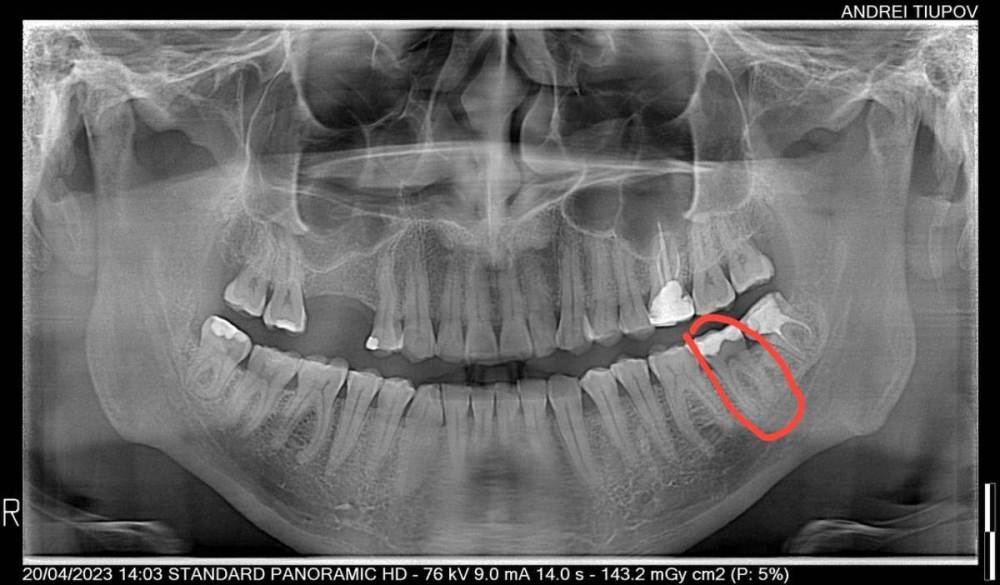

randomsctions Опубликовано 21 апреля, 2023 Поделиться Опубликовано 21 апреля, 2023 (изменено) Здравствуйте! Около 10 дней назад появилась стреляющая боль в верхней части челюсти слева. Сходил ко врачу (терапевту), результат: боли неясного характера. выписали дексаметазон и сказали наблюдать. На время стало меньше болеть. два дня назад сильно заболело в области, обведенной красным на снимке. Сначала казалось, что это зуб с большой пломбой, теперь, спустя два дня непрерывной интенсивной боли уже тяжело сказать, откуда именно исходит боль. Болит очень сильно, на 9 точно, почти невозможно терпеть. Не спал двое суток, и непонятно, когда удастся. Принимал по несколько таблеток кетарола, кетанова и ибупрофена, почти никакого эффекта, уснуть невозможно. вчера посетил утром другого врача (т.к. у первого не было номерков) - сделали снимок, сказали, точно не могут определить, с каким зубом проблема, и не хотят просто так пломбировать каналы здоровых зубов. Сказали, что боль может иррадиироваться от восьмёрок, и их можно попробовать удалить, но тоже не факт, что поможет. Выписали непраксен и антибиотики на 5 дней, записали на следующую неделю. Боль нестерпимая, поэтому в этот же день пошел в третью клинику. Надеялся, что удалят две восьмерки слева, и если боль не пройдёт, то уже смотреть дальше. Но врач отказалась удалять что-либо, а сказала, что 99%, что из-за стирания эмали и оголения дентина у зубов повысилась чувствительность, и отсюда боль (бруксизм у меня действительно есть, и зубы сильно стёрты, и часто реагируют на температуру или даже прикосновения). Покрыли сразу много зубов раствором для пломб, и отправили домой. В течение 2-3 часов я не чувствовал боль из-за анестезии (это были лучшие два часа за всё это время). Но сразу после этого разболелось ещё сильнее. Я уже не знаю, как мне это пережить, т.к. боль такая, что абсолютно невозможно уснуть. Уже готов удалить любое количество зубов, лишь бы избавиться от боли. Но если считать 4 обведенных красным зуба плюс пятый — 8ка снизу, то, как я понимаю, сразу 5 зубов удалять никто не станет. очень прошу подсказать, что тут можно сделать. Если это не решится за максимум ещё два дня, я не знаю, как я буду дальше. Не спать пятые сутки уже будет невозможно. Я готов удалить зуб(ы), но какой? Изменено 21 апреля, 2023 пользователем randomsctions Дополнение про бруксизм Ссылка на комментарий

randomsctions Опубликовано 24 апреля, 2023 Автор Поделиться Опубликовано 24 апреля, 2023 Добрый день! Наконец-то уговорил врачей сделать КТ. При постукивании, если внимательно прислушиваться, выделяется нижний зуб (обвел красным), ну и верхний депульпированный. Дантист быстро показала КТ эндодонтисту, оба врача ничего страшного там не увидели. Боль продолжается, в состоянии покоя снижается до 1-2, после еды или воды возрастает до 7-8, потом плавно возвращается к 1-2. 741021604_AndreiTiupovCBTCscan.dcm Ссылка на комментарий